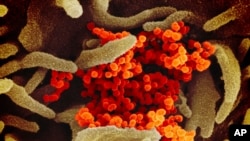

It’s a never-before-seen type of coronavirus, a large family of viruses that affect both animals and people. Some types cause the common cold. But two other types have caused severe disease outbreaks before: SARS, or severe acute respiratory syndrome, in late 2002, and MERS, or Middle East respiratory syndrome, which first appeared in 2012.

The World Health Organization officially named the new illness COVID-19, reflecting that it’s a new coronavirus that emerged late last year. Common symptoms include fever, cough and shortness of breath. While serious cases can turn into pneumonia, most patients appear to have a fairly mild illness.